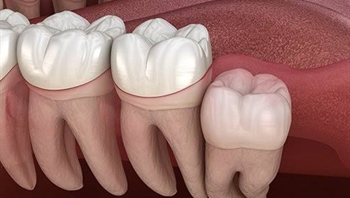

Wisdom teeth often known as third molars are the last teeth to erupt. One usually gets them in late teens or early twenties. However, even instances of eruption in late adulthood are common. If they erupt smoothly and without any interruption, then they can be proved as an asset. But the problem with third molars is that in case they do not erupt properly or are misaligned, they would need to be extracted. If they are poorly aligned, then they can damage the adjacent teeth.

It is also possible that wisdom tooth is impacted. This means that the wisdom teeth remain intact in the soft tissue and partially break or erupt through gums. If they remain partially open, then the chances of bacteria entering the tooth are high which may cause infection & lead to the swelling in the jaw, pain and general illness.

It is not necessary to remove wisdom teeth as long as they are not causing any problem. They would have to be removed if they are impacted or causing crowding. If you do not remove the wisdom tooth, it will be impacted. Your mouth might not provide space for it to erupt as a result it will erupt at the wrong angle which can damage the adjacent tooth.